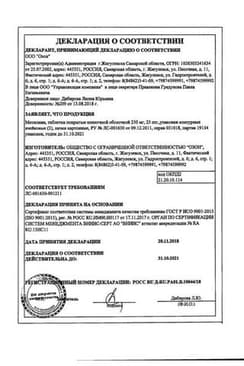

Сертификаты